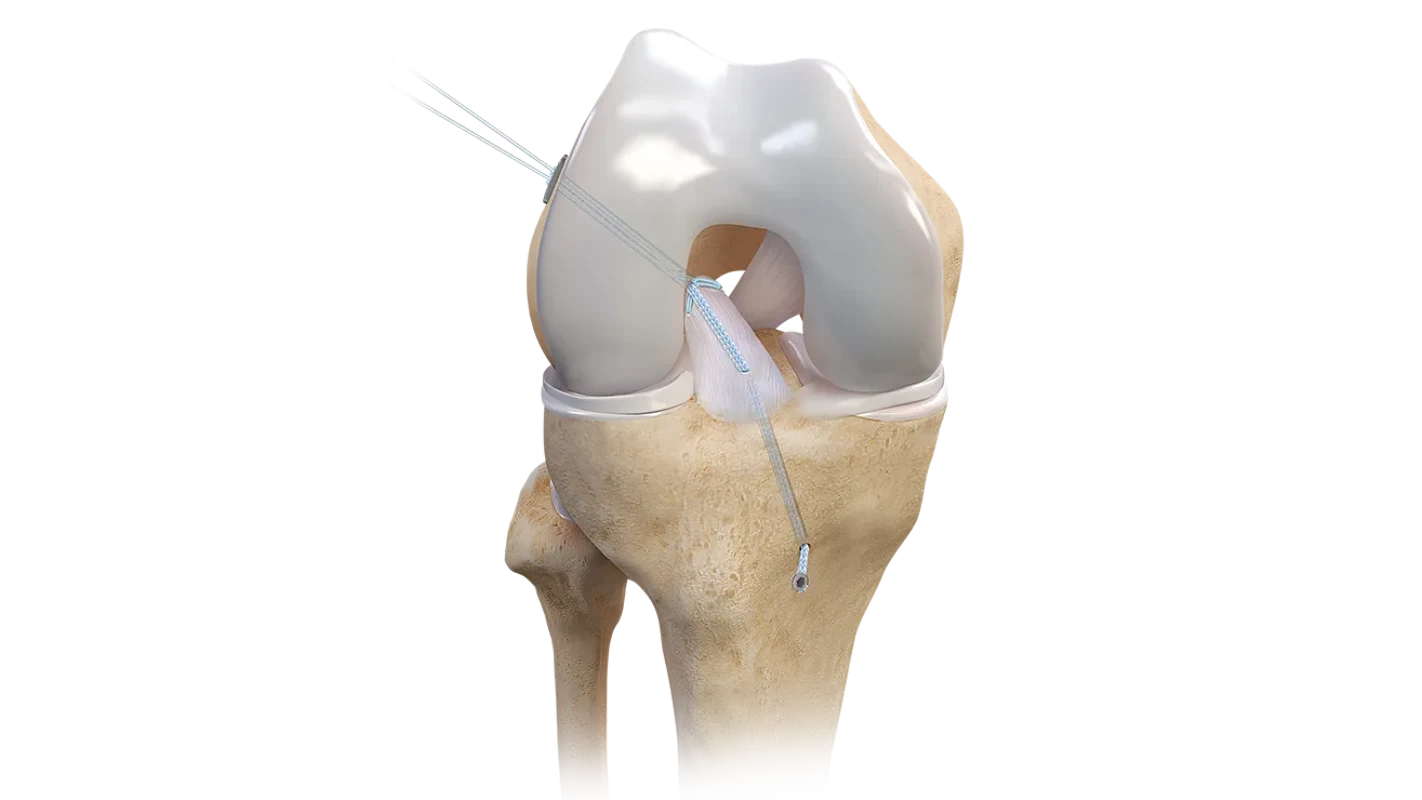

Arthrex es líder global en soluciones para artroscopía y medicina deportiva, ofreciendo implantes, suturas e instrumentación desarrollados para lograr reparaciones más fuertes, reconstrucciones anatómicas y una recuperación más rápida del paciente. Nuestro portafolio cubre hombro, rodilla, tobillo y muñeca, con tecnología de última generación para cada procedimiento.

- Implantes para reconstrucción de LCA/LCP

- Reconstrucción multiligamentaria